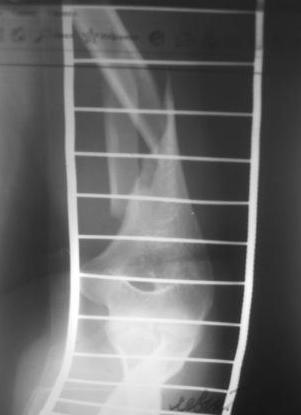

[Ortho] Перелом н\3 плечевой кости. Тактика лечения?

Перелом нестабильный, тактика - если позволяет сосояние больной, оперативное лечение. Как пример см. ниже, можно без скобы - стяжки с ЭПФ. Представленный способ, функциональный, данная больная в качестве внешней иммобиллизации в течение 3-х недель полльзовалась косыночной повязкой, востановление функции плеча полное. Правда травма изолированная, но операция выполнялась через три недели после травмы, тот час после обращения ко мне - иногородняя.